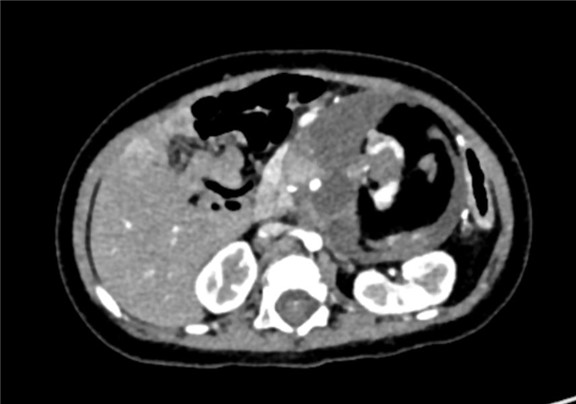

下腹部增强CT示:腹腔巨大占位,考虑畸胎瘤可能性大

术前CT检查:

平衡期